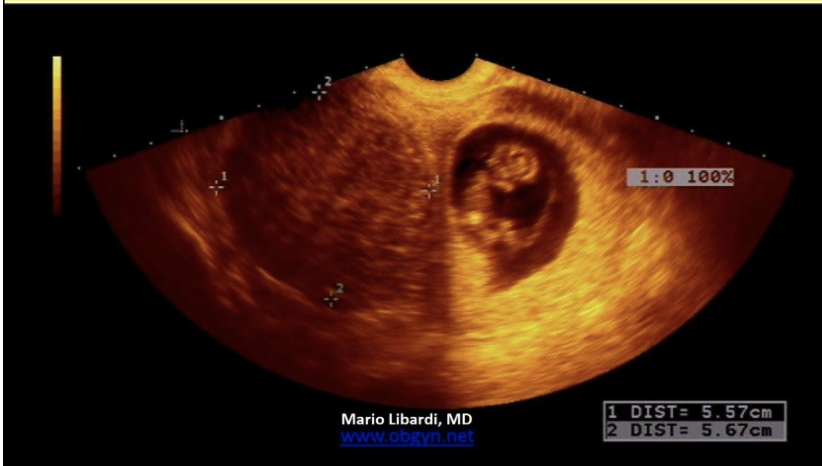

a pt has fetal dating w/hx of LMP 5-6 weeks + serum bHCG of 3,000 units/mL (IRP).

. anything over 2,000 units/mL

TV US shows a thickened endometrium at 20mm, but no GS. What is the next step

.

a) repeat only the serum bHCG in 5-7 days

b) closely evaluate adnexa for ectopic pregnancy

c) repeat only the US exam in 5-7 days

d) repeat serum bHCG and US in 5-7 days